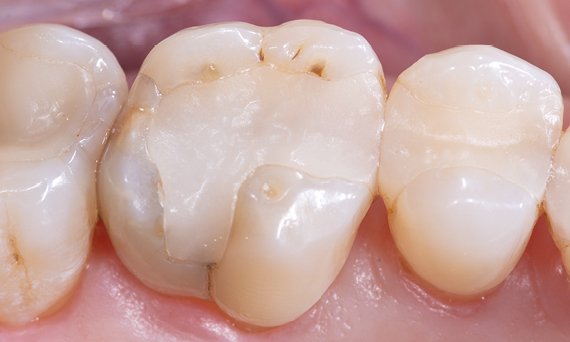

Composite filling, tooth 16, before CEREC treatment

Before

Large insufficiency of the composite filling on tooth 16 with distal marginal ridge cracks, a lingual wall crack and distal recurrent decay.

After

Highly esthetic full-surface glass-ceramic crown.